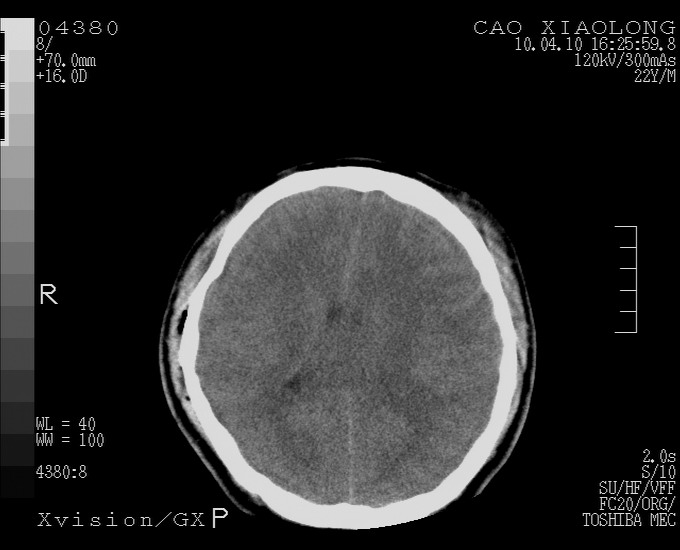

以下是引用随光逐影在2010-4-11 11:00:00的发言:[br]1)左侧额颞顶部硬膜下血肿。2)蛛网膜下腔出血。3)右侧颞顶部颅骨线形骨折。[br][br]20小时后复查:左侧额颞叶脑挫裂伤;左侧额颞顶部硬膜下血肿及蛛网膜下腔出血有吸收表现;右侧颞顶部颅骨线形骨折。[br]